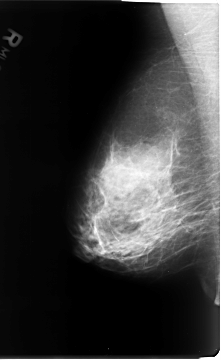

B_3072_1.RIGHT_CC

RIGHT_CC LINES 4744 PIXELS_PER_LINE 2984 BITS_PER_PIXEL 12 RESOLUTION 50 NON_OVERLAY